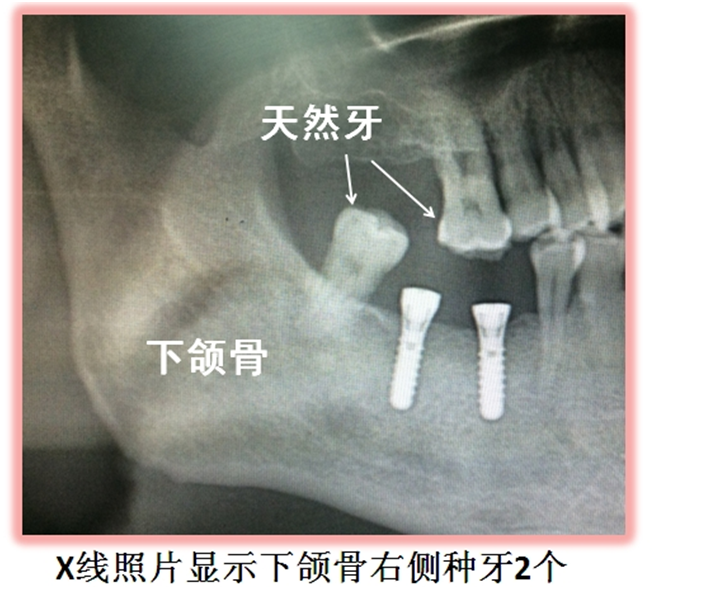

3、種植牙是全口做,不能單做論

前麵說過了,種植牙適應症廣泛,適合單個(ge) 牙齒缺失、多個(ge) 牙齒缺失、半口以及全口牙齒缺失的修複,所以牙齒缺失後,可以先到醫院檢查確定是否可以做種植牙。